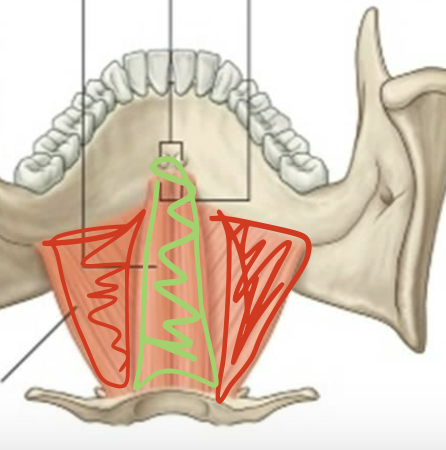

What is the muscle in red?

Mylohyoid (elevate hyoid, depress mandible)

What is this muscle in green?

Geniohyoid (elevate hyoid, depress mandible)